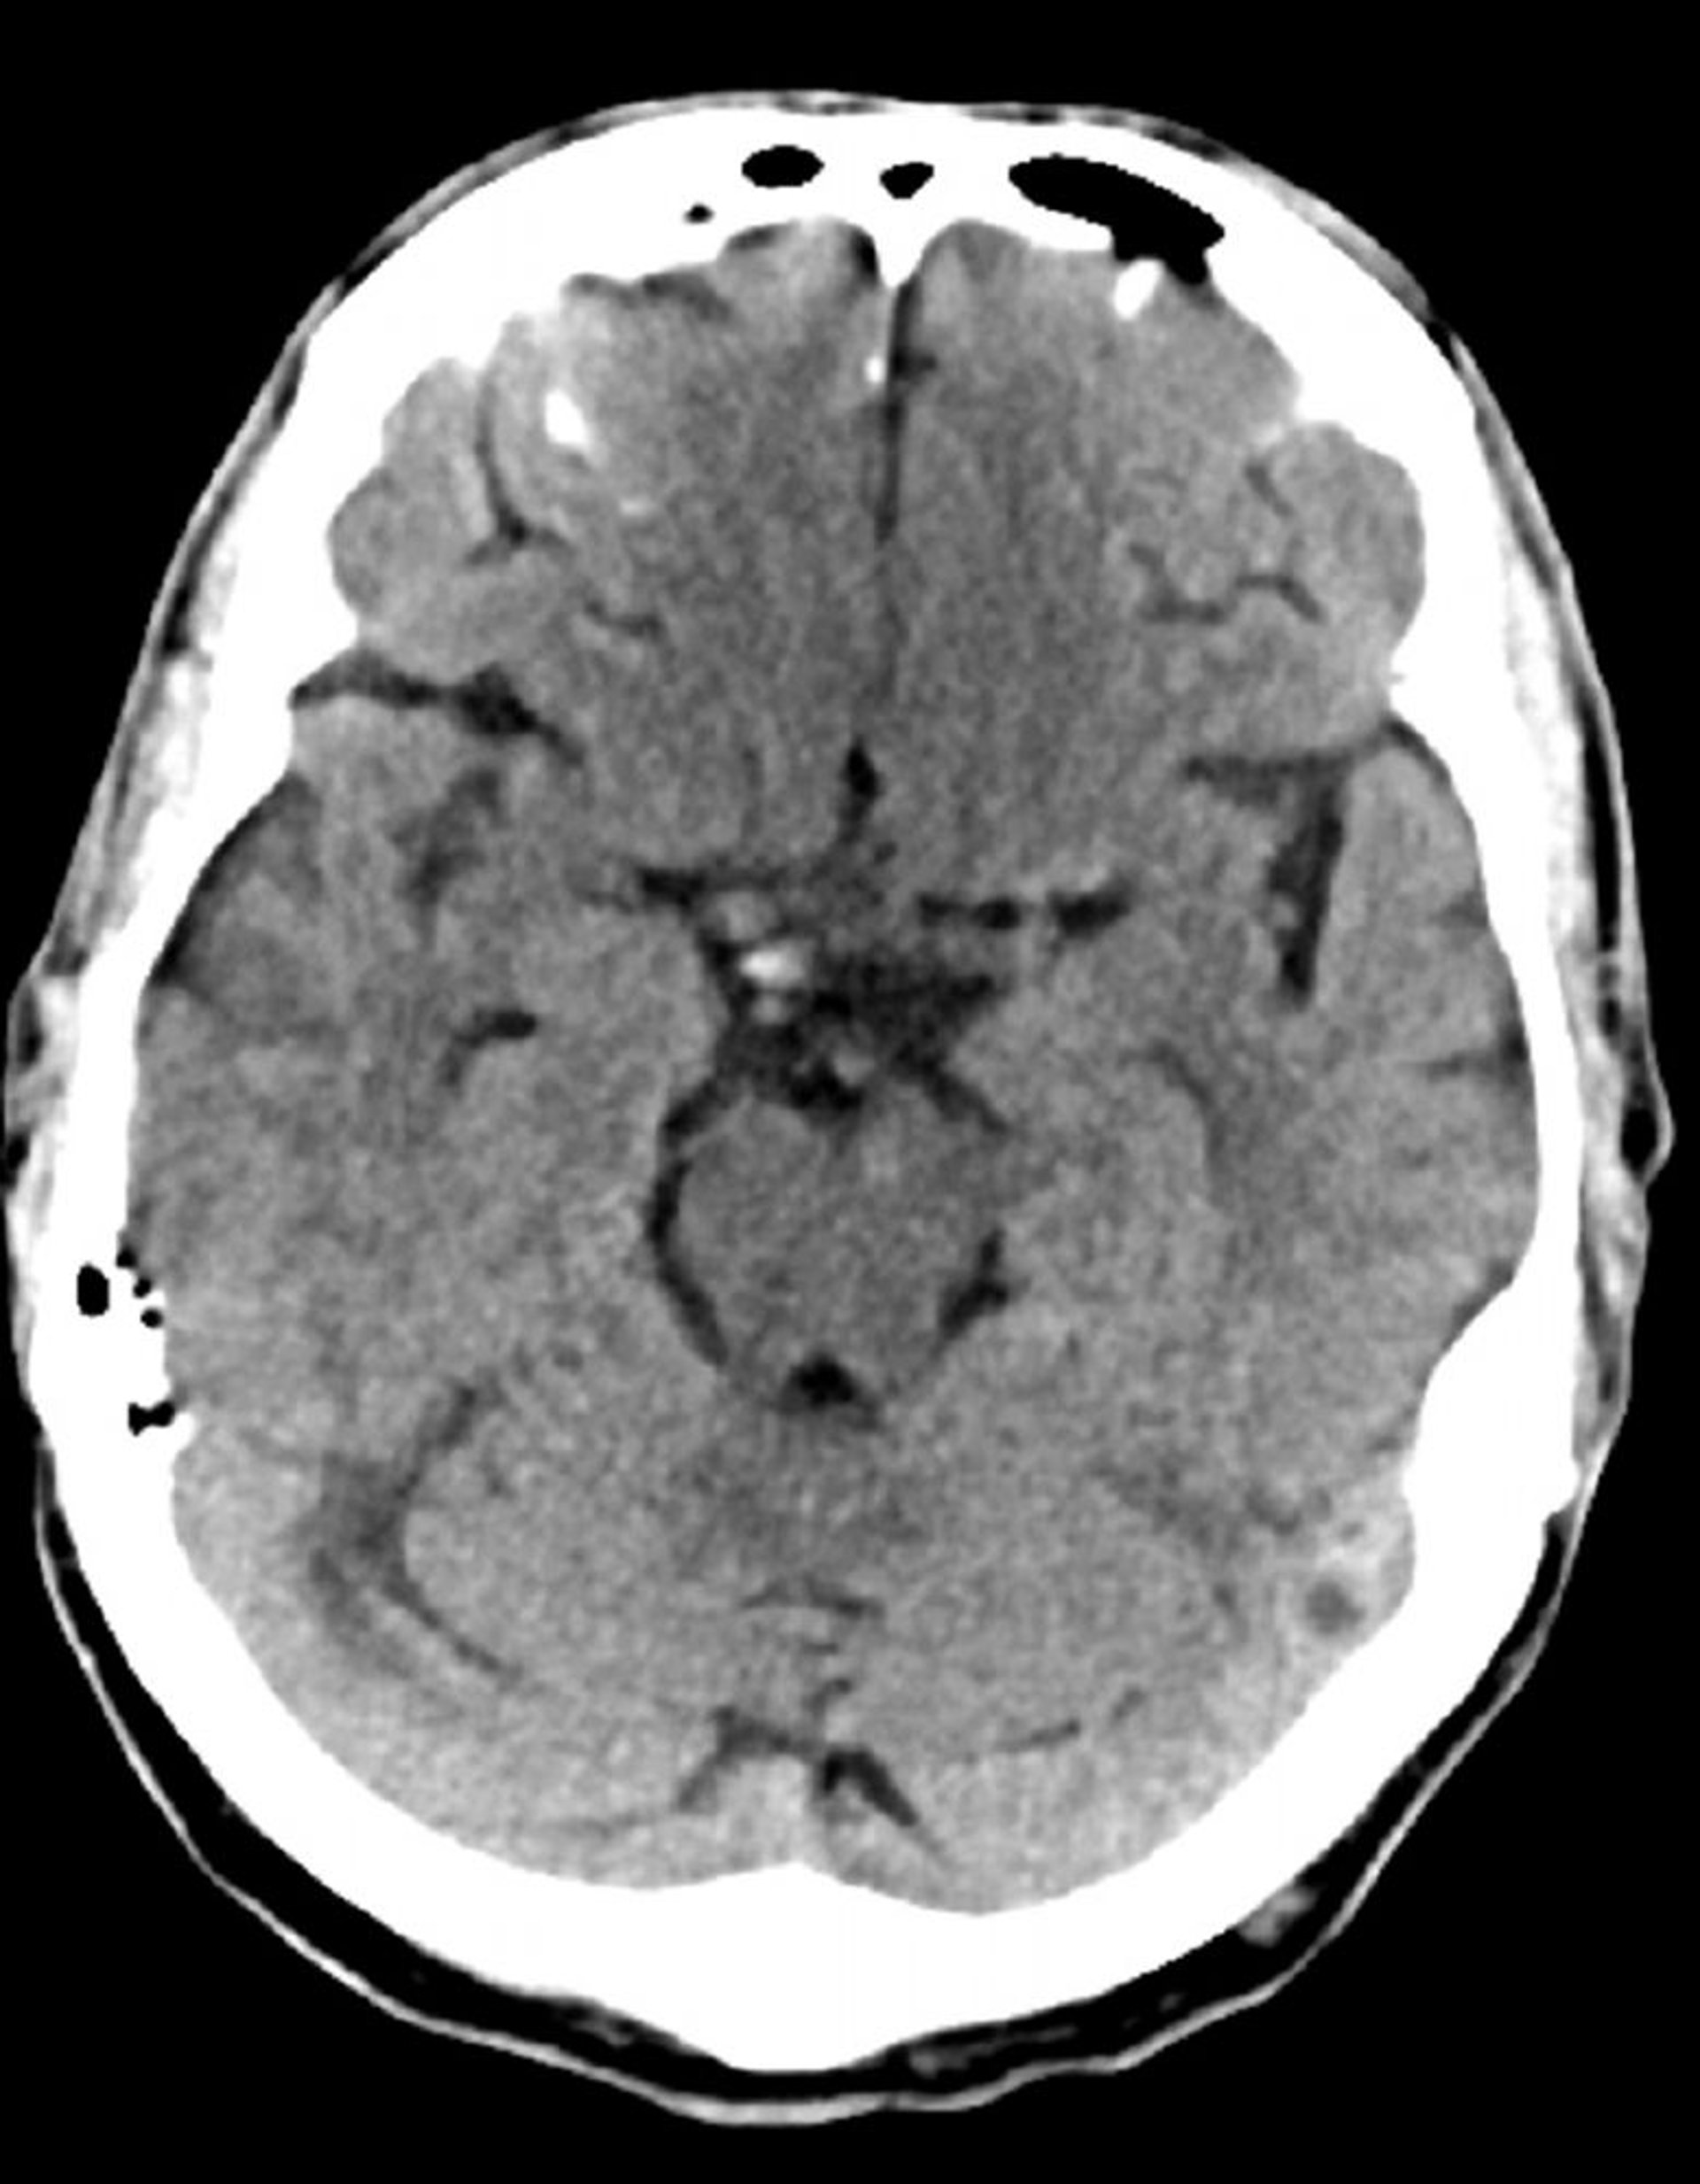

Normaler Kopf-CT-Scan (Erwachsener 74) - Folie 7

Dieses Bild ist ein normaler CT-Scan des Kopfes eines Erwachsenen im Alter von 74 Jahren. Verglichen mit dem normalen CT-Scan eines 30-jährigen Kopfes sind die Ventrikel und die Sulci größer. Diese Ergebnisse sind in dieser Altersgruppe normal.